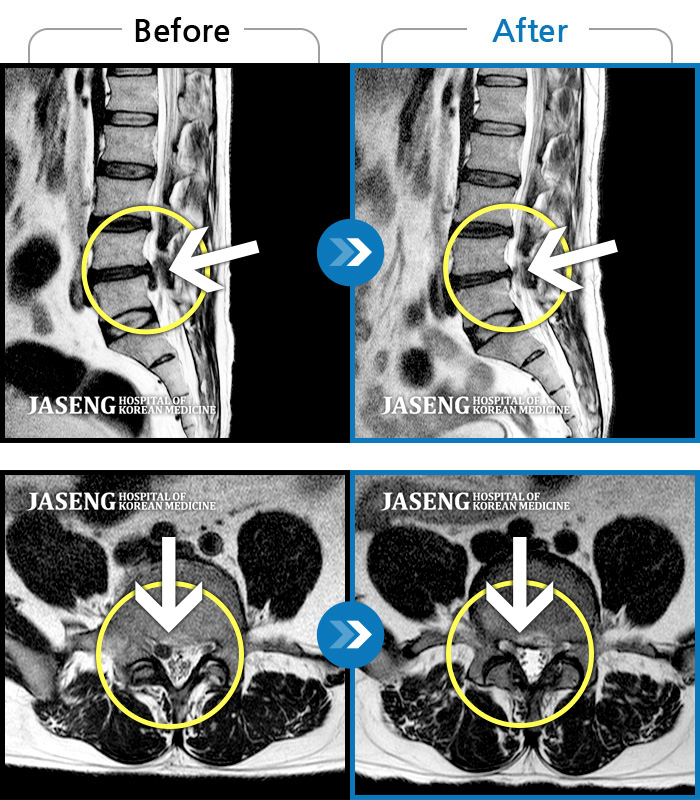

Before

After

통증 및 우측 엉치 우측 종아리 땡기는 통증이 심하여 일상생활이 안되는 상태로 내원하셨던 분입니다.

2023.11.21 ~ 2024.06.05